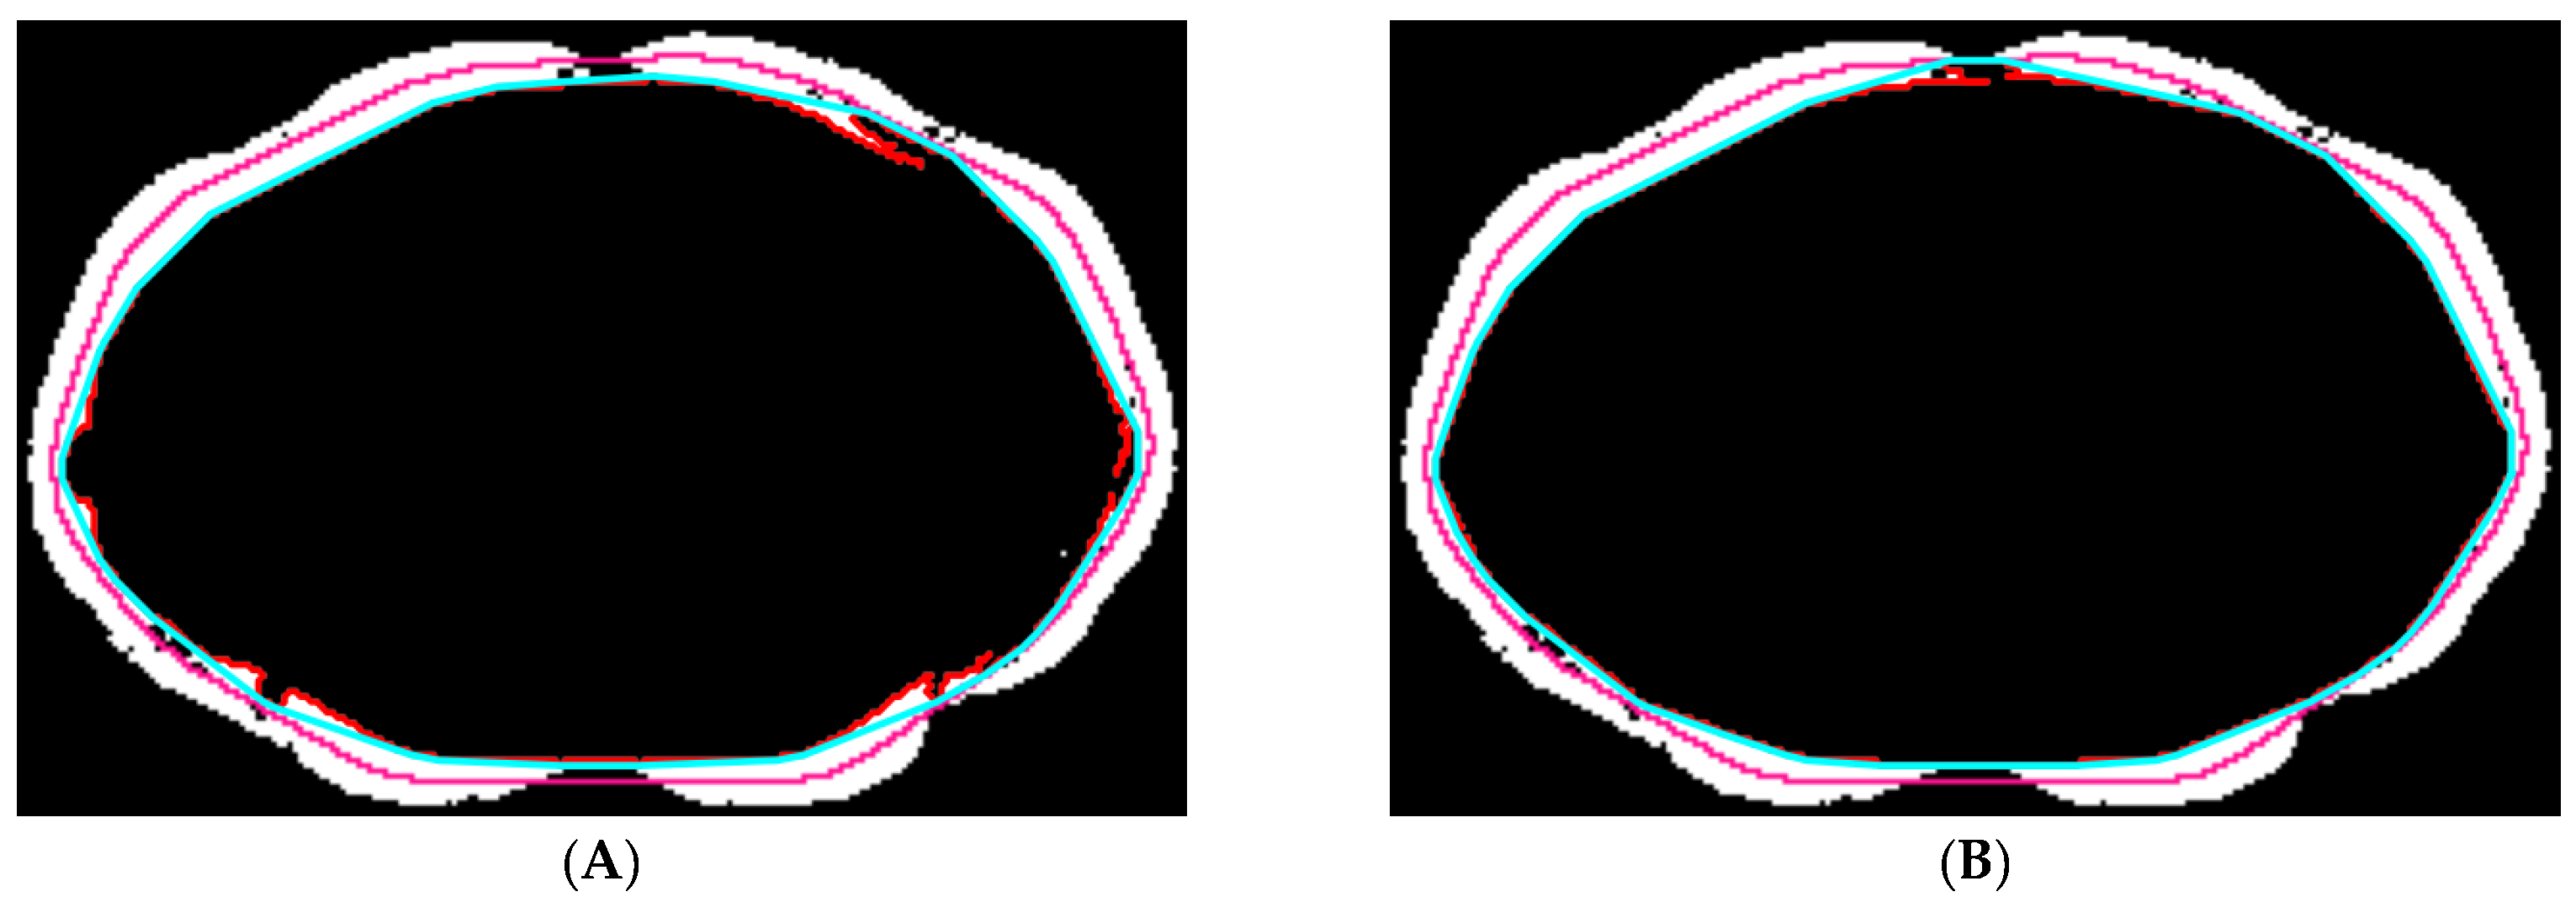

2.5.2. Abdominal Muscle Segmentation

2.5.3. Paraspinal Muscle Segmentation